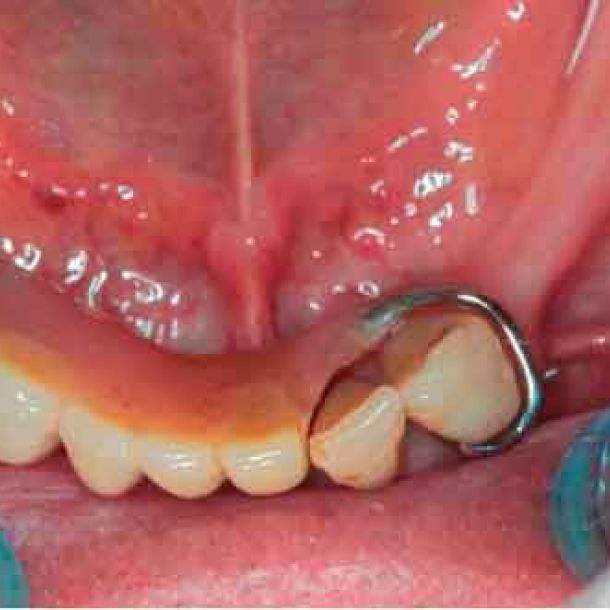

Avant d'acquérir le CBCT, j'ai ajouté 2 morceaux de composite à la mandibule pour pouvoir effectuer le processus de picking pendant le protocole MODJAW. Il s'agit d'une astuce utile à retenir en cas d'absence de dents.

Fixez la fourchet paraocclusale à la mandibule du patient

Sélectionnez les points précédents dans la bouche du patient à l'aide du Tally (stylet)